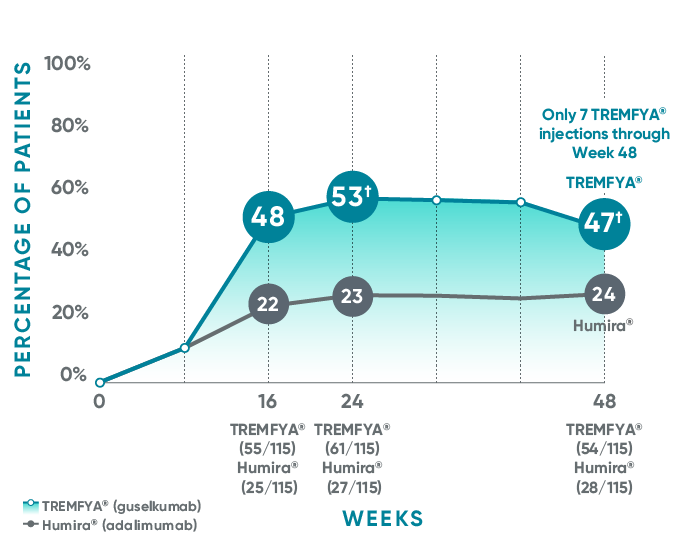

VOYAGE 1: Post hoc analysis PASI 100 response at Weeks 16, 24, and 48 (NRI)*†

*PASI 100 was a post hoc analysis that was not adjusted for multiplicity: P values were considered nominal.

The same patients may not have responded at each time point.

VOYAGE co-primary endpoints at Week 16 (NRI)1,2:

VOYAGE 1—PASI 90: TREMFYA® 73% (241/329), placebo 3% (5/174) (P<0.001). IGA 0/1: TREMFYA® 85% (280/329), placebo 7% (12/174) (P<0.001).

VOYAGE 2—PASI 90: TREMFYA® 70% (347/496), placebo 2% (6/248) (P<0.001). IGA 0/1: TREMFYA® 84% (417/496), placebo 8% (21/248) (P<0.001).

†Results from North American sites only, which used US-licensed Humira®.

Humira is a registered trademark of Abbvie Biotechnology Ltd. Corporation.

NRI=nonresponder imputation; PASI 100=proportion of patients who achieved 100% reduction (or improvement) in PASI score from baseline.

References: 1. Data on file. Janssen Biotech, Inc. 2. TREMFYA® (guselkumab) [Prescribing Information]. Horsham, PA: Janssen Biotech, Inc.